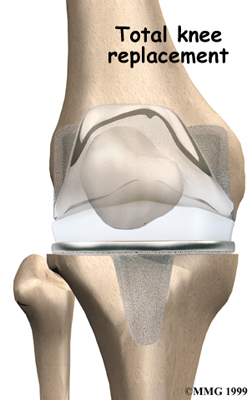

Artificial Knee Replacement

An artificial knee replacement is the ultimate solution for advanced knee OA.

Surgeons prefer not to put a new knee joint in patients younger than 60. This is because younger patients are generally more active and might put too much stress on the joint, causing it to loosen or even crack. A revision surgery to replace a damaged prosthesis is harder to do, has more possible complications, and is usually less successful than a first-time joint replacement surgery.

Related Document: FYZICAL Aurora's Guide to Artificial Joint Replacement of the Knee